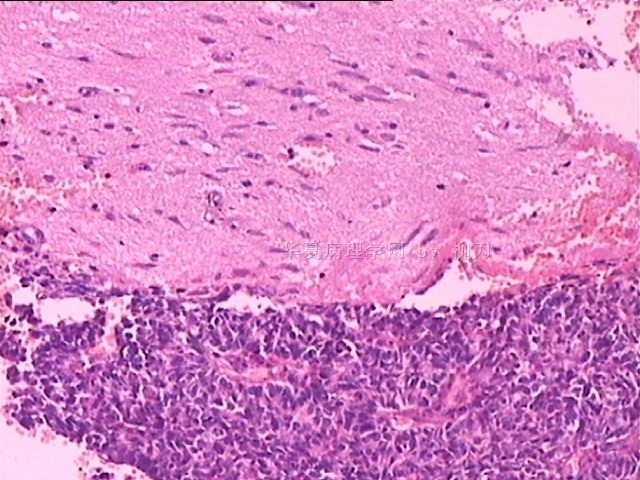

女,34y,头痛一月,右额叶占位:5*5*4cm。囊性区域,4cm。大体:3.5x3x1cm灰白间暗褐色组织一堆,质嫩。临床诊断1:胶质瘤,2:血管母细胞瘤。

本人县级医院头颅手术少,考虑胶质母细胞瘤。大家指导指导。

胶母

同意胶质母细胞瘤。细胞异型、坏死、核分裂、血管内皮肿胀增生均可见到。

This is certainly a WHO grade IV malignant neoplasm. While most likely a glioblastoma, I would carefully rule out PNET by staining for GFAP and neuronal markers such as synaptophysin, NeuN and NSE. Rarely, PNET may shows marked pleomorphism and indistinguishable from glioblastoma on HE stain.

同意马老师的意见,该肿瘤从形态及年龄来看考虑PNET或GBM,须标记Syn、NSE、S-100、NeuN和GFAP来鉴别。

结合图片细胞形态特点考虑胶质母细胞瘤,组化标记排除其他